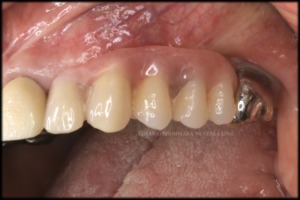

治療後

手術部位が生着したのを確認後、インプラント体の上部にロケーターアタッチメントを取り付け、新しく作製した義歯を装着しました。

義歯装着後は、主訴にあった疼痛や違和感はなくなり、快適にお過ごしいただいています。